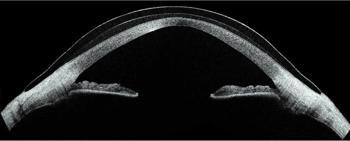

The latest development is completely customisable wavefront-guided scleral lenses. This form of correction is targeted to the patient’s residual aberration profile and requires the reliable determination of specific HOA terms. To create these lenses, wavefront aberrometry is performed to capture the aberrations of the individual wearing a marked conventional scleral lens (Fig 5 see pic at the top). The inverse of this wavefront is then applied to counteract the residual aberration through destructive interference on the front surface of a new lens. Recent studies have shown the majority of patients prefer these lenses to conventional scleral lenses11.

This level of precision doesn’t come easily. Firstly, the completely customisable wavefront-guided scleral lenses must be rotationally stable, with limited movement. It also costs more than a conventional scleral lens, requires a specialised aberrometer and typically requires more chair time. But, for the right patient, the benefits far outweigh the hurdles.